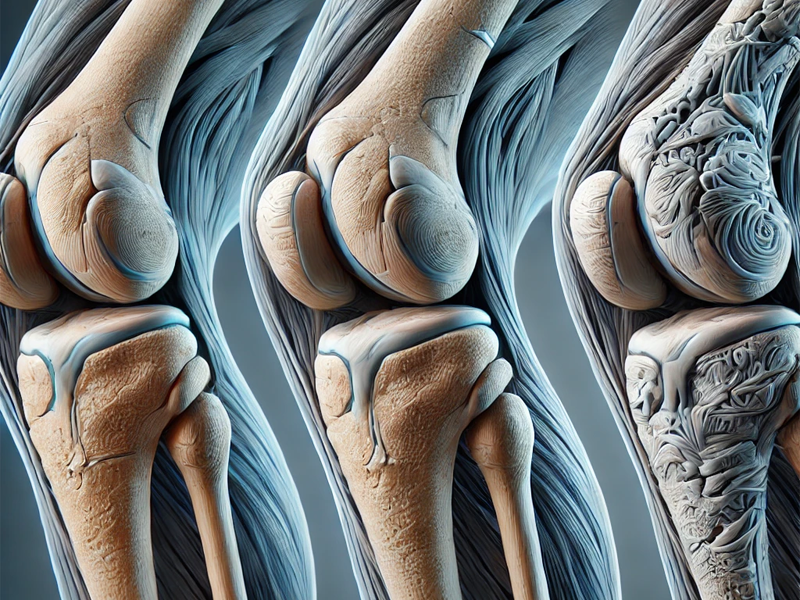

آسیبهای غضروفی یکی از مشکلات شایع در مفاصل بدن به ویژه زانو، لگن و مچ پا است که اغلب با درد و محدودیتهای حرکتی همراه است. پیوند غضروف به عنوان یک روش درمانی نوین و موثر در حوزه ارتوپدی و پزشکی بازساختی شناخته میشود که به منظور بازسازی بافت غضروفی آسیبدیده و بازگرداندن عملکرد طبیعی […]